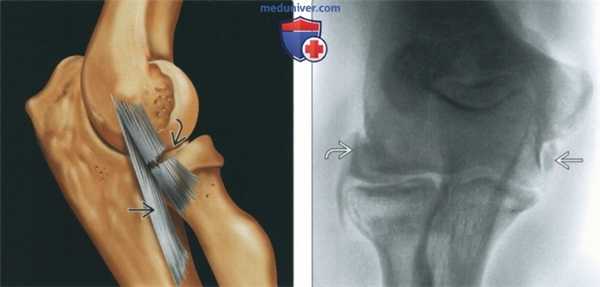

(Слева) На рисунке лучевой коллатеральной связки показано ее прерывание в средней части. Большинство разрывов связки встречаются между началом и средней частью связки. Латеральная локтевая коллатеральная связка интактна.

(Справа) На фронтальной MPT Т2 ВИ FS, полученной при низком магнитном поле, определяется слабо выраженный частичный разрыв лучевой коллатеральной связки с повышенным сигналом от волокон связки и с едва заметным разрывом связки. Кроме того, имеется растяжение латеральной локтевой коллатеральной связки. Общее сухожилие разгибателя интактно. (Слева) На фронтальной МРТ PD ВИ FS у юноши 20 лет определяется полный разрыв начала лучевой коллатеральной связки после падения. Прилежащее сухожилие общего разгибателя отслоилось от надмыщелка. В середине сустава в поле зрения попадает вся головка лучевой кости по ширине, а также локтевая коллатеральная связка, следовательно, в поле зрения должна быть лучевая коллатеральная связка, а не латеральная локтевая коллатеральная связка.

(Слева) Рисунок, латеральная поверхность локтевого сустава: показан разрыв средней трети лучевой коллатеральной связки (ЛуКС). При этом целостность лучелоктевой коллатеральной связки (ЛЛоКС) сохранена.

(Справа) Артрография, передне-задняя проекция: определяются разрывы как ЛуКС, так и ЛЛоКС, обусловленные вывихом. Контрастный препарат скапливается между разорванными концами связок и прилежащими мышцами.